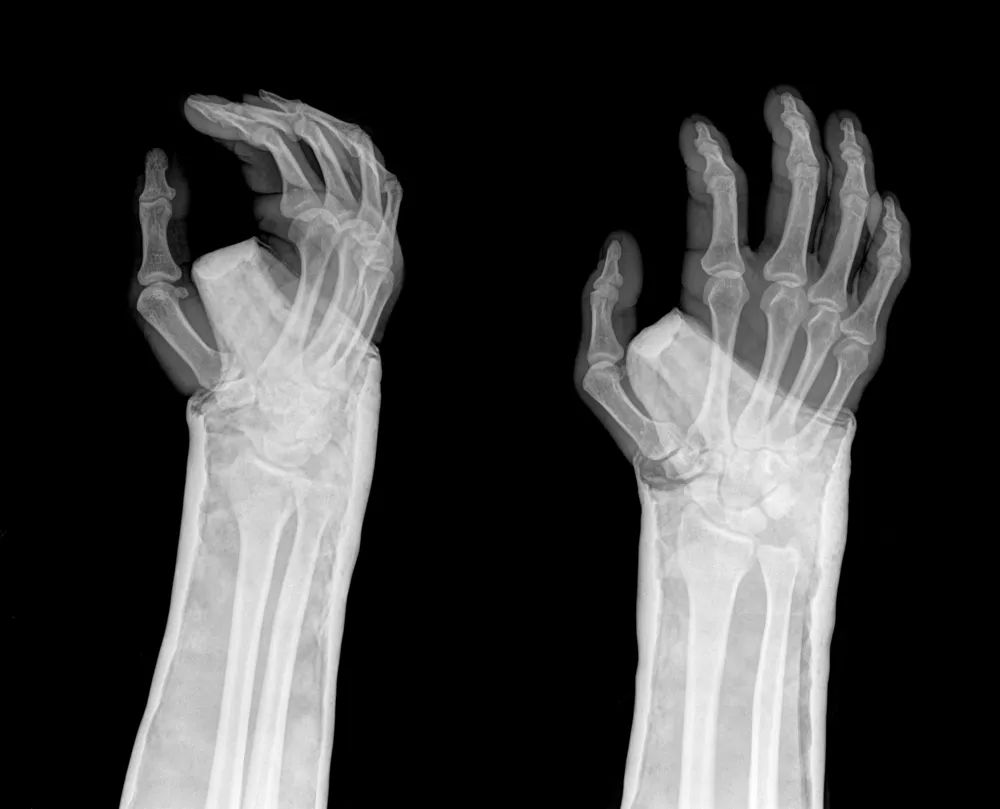

桡骨远端关节面呈由背侧向掌侧、由桡侧向尺侧的凹面, 分别形成掌倾角 (10°~15°) 和尺倾角 (20°~25°)。

桡骨茎突尺侧与尺骨小头桡侧构成尺桡下关节, 与尺桡上关节一起,构成前臂旋转活动的解剖学基础。